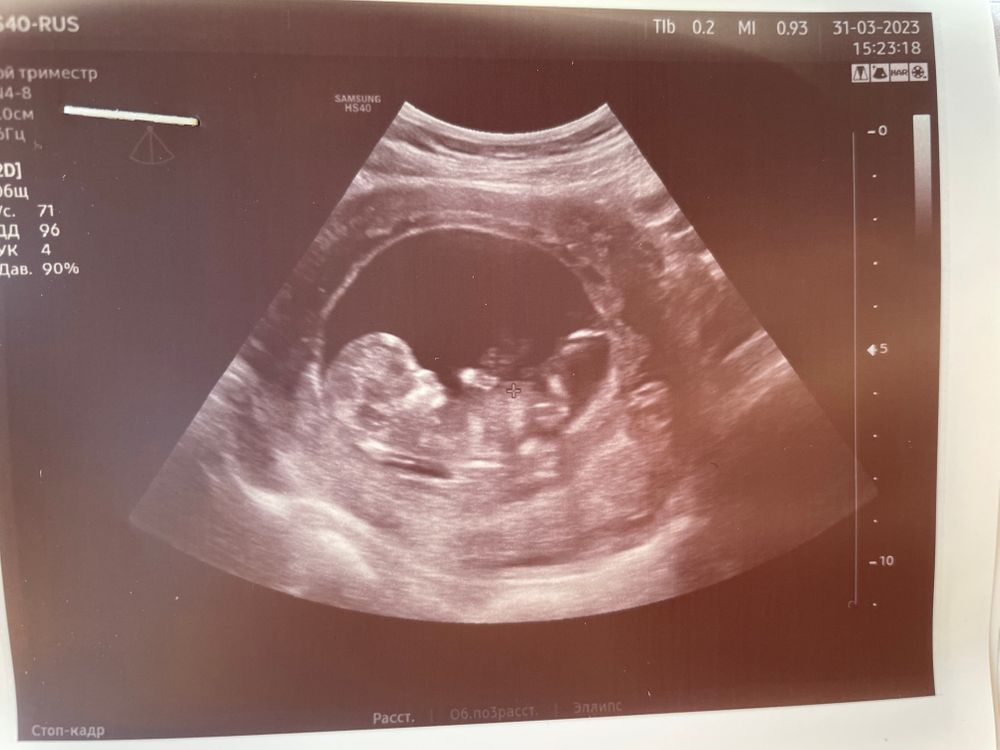

Ну что же, первый скрининг прошел, пока жду еще кровь, но есть результаты узи. Узист была немногословна, потому не знаю все ли в порядке, конечно же полезла смотреть информацию по нормам в интернете. Срок по месячным 12 недель. Длина Носовой 1,9 шеи 1,1 при том что остальные показатели идут с небольшим опережением на 12,2-12,5. Переживаю из-за носика.

Хочется услышать какая длинна Носовой кости на первом скрининге была у вас? Здоров ли был ребенок по итогу?